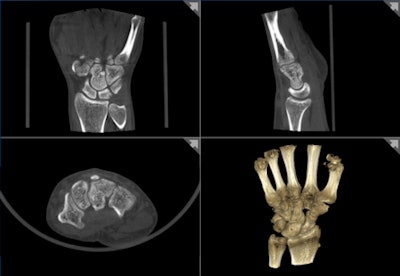

![]() |

| 3D CT volume rendering acquired on Planmed's Verity extremity scanner aids orthopedic treatment monitoring and planning. |

Verity acquires imaging data volumetrically in a single rotation, in contrast to multiple rotations during MDCT. A routine knee exam can be completed in about five minutes, with actual image acquisition consuming only about 20 seconds, he said. 3D volumetric reconstructions can be performed at the console or ported to a PACS for processing and analysis.

Tohka envisions a role for Verity in radiology, orthopedics, sports medicine, and podiatry. Verity can visualize degenerative bone and joint diseases, such as osteoarthritis and various foot injuries and diseases.